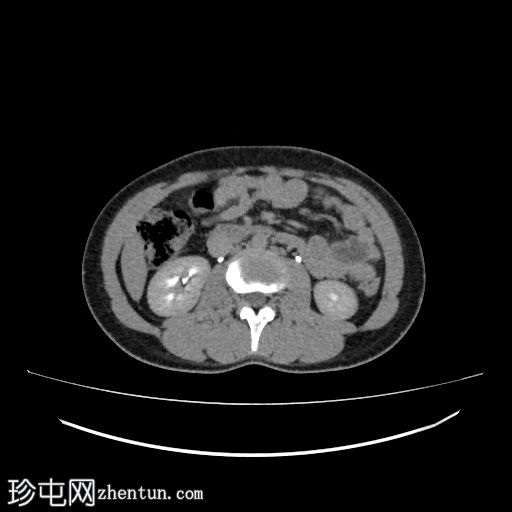

肾轴位

排泄期

3.jpg

右侧输尿管近端至中段在L3-L5椎体水平向内侧移位

输尿管在L3-L4椎体水平轻度节段性隆起

该段输尿管走行于下腔静脉后方,然后从主动脉和下腔静脉之间向内侧走行,远端转向外侧,正常开口于膀胱输尿管连接处

上中段未显影

远端显影的输尿管走行正常,通向膀胱

右侧输尿管走行异常,属于环腔静脉/腔后输尿管(2型)

影像学上,该畸形可分为两种类型。 1 型是较常见的类型,表现为近端输尿管明显向内侧偏移,呈经典的“S”形或“鱼钩”形,并伴有肾积水。2 型较少见,表现为输尿管袢位置较高,梗阻程度较轻,呈镰刀状。过去主要通过静脉尿路造影进行诊断,而现在 CT 尿路造影和 MR 尿路造影能够更清晰地显示输尿管与下腔静脉的关系以及梗阻程度。